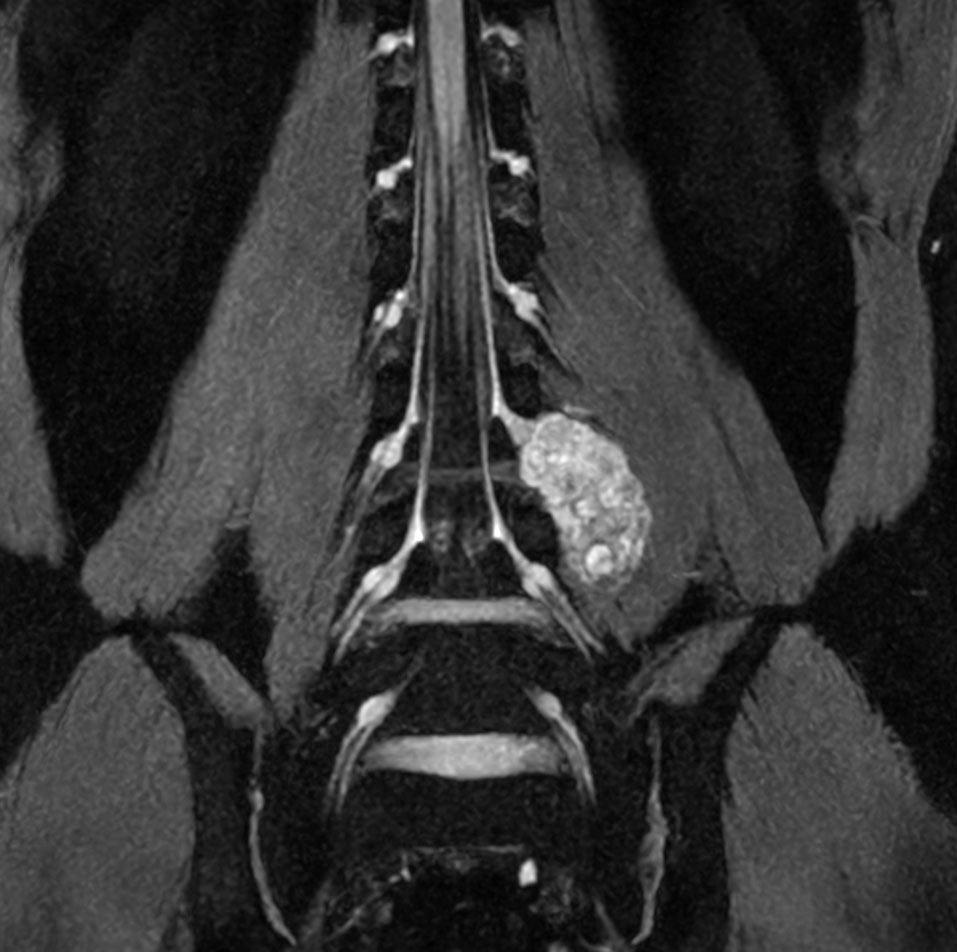

Neurography schwannoma (Compressed SENSE)

Patient with a lumbar neurography schwannoma.